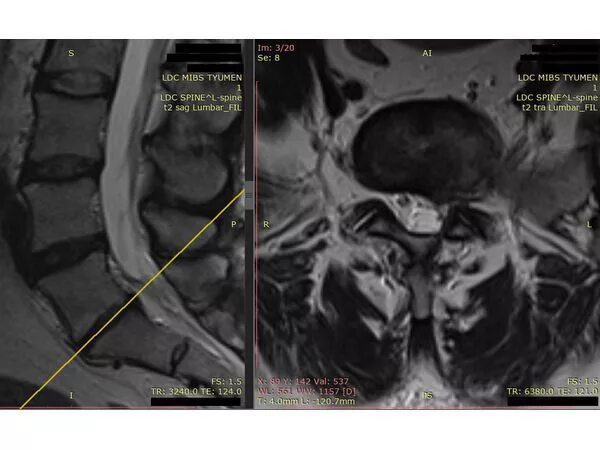

Операция грыжа l5 s1